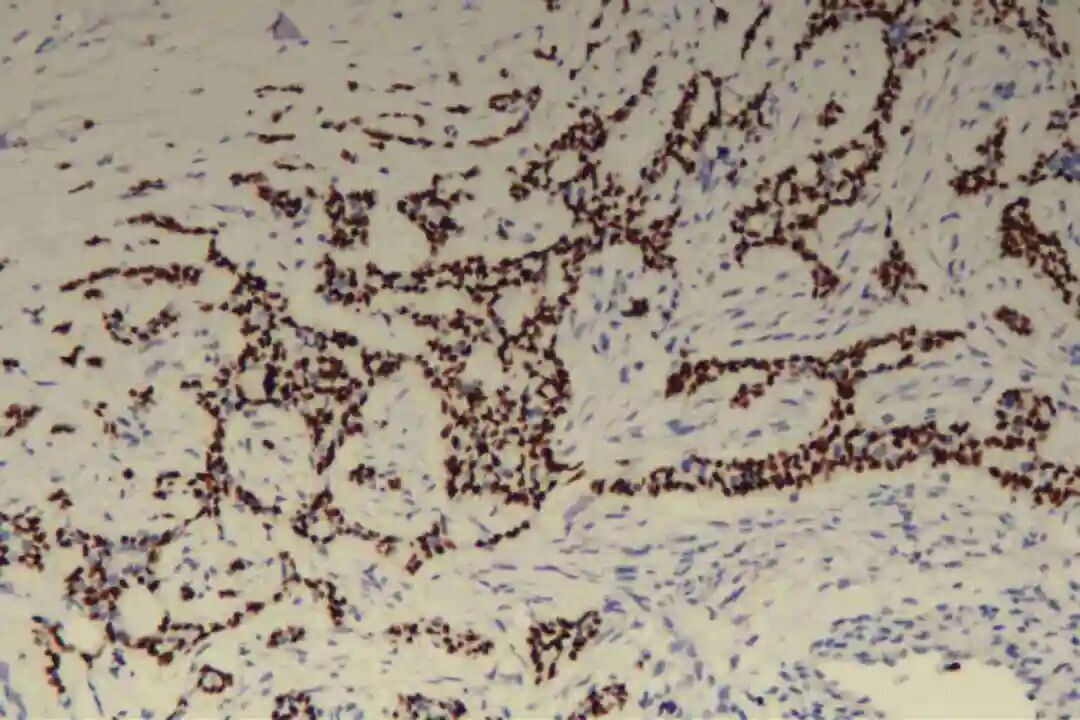

肌上皮细胞是PACC的重要组成部分,其标志物表达是诊断PACC的关键,主要表达p63、P40、平滑肌肌动蛋白(SMA)、肌动蛋白(Actin)及S-100蛋白,其中p63、P40呈弥漫阳性表达,SMA、S-100蛋白呈局灶或弥漫阳性表达。

Ki-67增殖指数:整体较低,一般为5%-20%,实体型区域Ki-67指数略高于经典型区域(可达到10%-25%),但均低于其他高危型乳腺癌(如浸润性导管癌,Ki-67指数多≥30%),这与PACC惰性生长的临床特点一致,也是评估预后的重要参考指标。